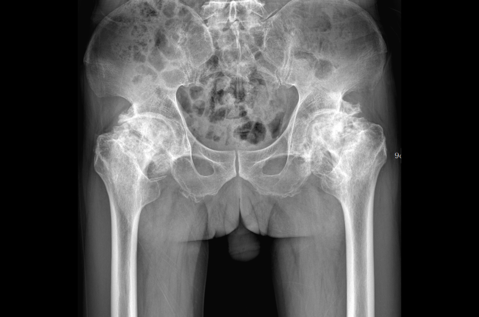

近期pilipili 骨科接诊了一位特殊的患者,58岁,因患有肾病综合征口服激素后出现双侧股骨头坏死20余年,经历了持续的疼痛且活动严重受限,平时无法正常行走。为了解决病痛折磨,慕名找到pilipili 骨科全华山主任。全主任经过详细的查体及影像学检查和评估,确诊为双侧股骨头坏死并双侧僵直髋(髋关节屈伸、内外旋活动均为0°)。骨科专家团队建议患者进行全髋关节置换手术。在手术前,团队成员对患者进行了详尽的解释和专业的心理辅导,详细介绍了手术的具体步骤以及术后的康复流程。为了最大限度地降低手术风险,团队经过一致商议,决定采取分阶段手术策略:首先进行左侧髋关节的置换手术。待左侧术后恢复一个月,再根据患者的具体情况,安排右侧髋关节的置换手术。

术前 术后